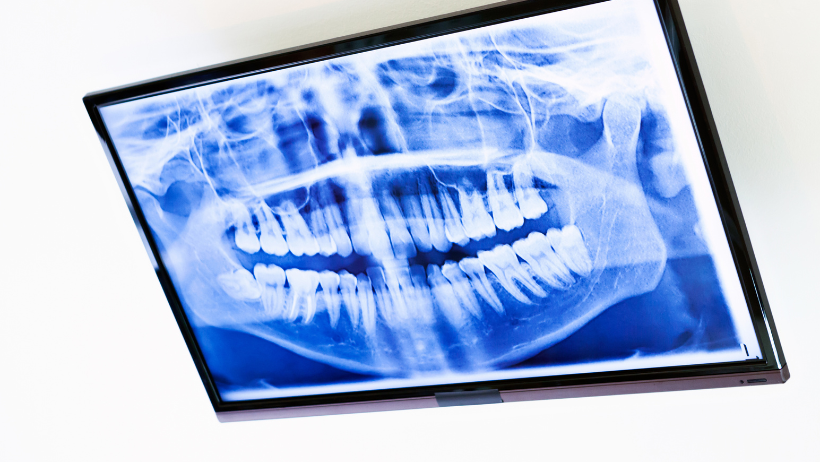

- Технология 3D-моделирования улыбки. Благодаря интраоральному сканеру врач-стоматолог делает абсолютно точные цифровые отпечатки ваших зубов, даже не касаясь их (на расстоянии 5-10 мм от зубов), изображения передаются на компьютер и формируются в точную копию вашей полости рта. Процедура занимает до 10 мин для обеих челюстей. Такая цифровая модель челюсти позволяет не только избежать неприятной процедуры создания гипсовых отпечатков, но и улучшает качество множества стоматологических процедур. Благодаря виртуальной модели ваших зубов, выведенной на экран, врач-стоматолог показывает пациенту кариозную полость и наглядно объясняет план лечения. Также сканер является незаменимым помощником в таких процедурах как установка виниров, коронок, накладок, имплантации зубов. К тому же, цифровая модель ваших зубов хранится в компьютере, и при необходимости, к ней можно возвращаться, чтобы сравнить изменения или восстанавливать точную форму зубов в случае их потери или истирания.

На основе вашего цифрового отпечатка и компьютерной томографии коронки зуба врачи могут определить даже угол наклона, под которым врачу нужно поставить имплант. Снятые размеры используются для точной установки импланта во время цифровой имплантации зубов.

- Компьютерный томограф последнего поколения обеспечивает полную 3D-диагностику состояния мягких и твердых тканей полости рта.